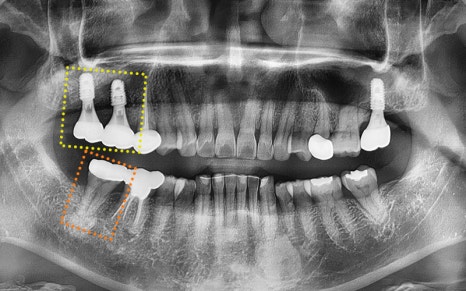

✅ 전 > 후

2024.11.22

▼ ▼ ▼

2025.04.15

서울오브치과병원은

늘 상대 치아와 평행하게,

잘 맞물리는 위치에

임플란트를 식립하는 원칙을 지키고 있습니다.

식립 후 한달체크때

별다른 이상이 없는것을 확인해주었고